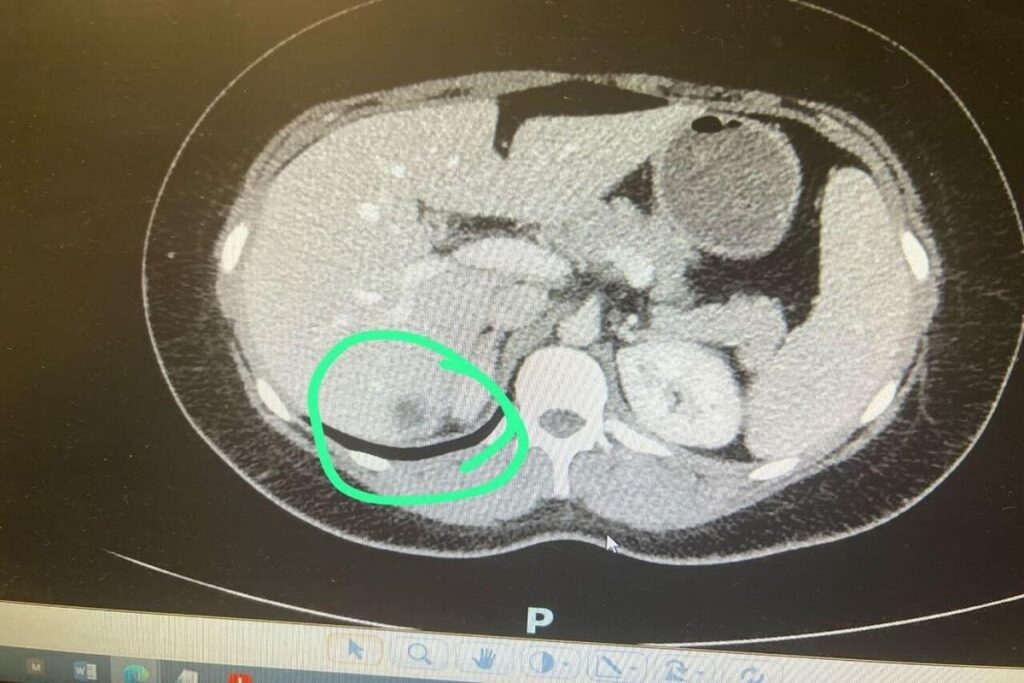

MRI जांच करने वाले रेडियोलॉजिस्ट डॉ. केके गुप्ता ने बताया, “यह एक पुष्ट 12 सप्ताह की गर्भावस्था थी, जो गर्भाशय में नहीं, बल्कि लिवर के दाहिने लोब में स्थित थी। हमने भ्रूण की हार्टबीट भी दर्ज की।” उन्होंने यह स्कैन 22 जुलाई को किया था। डॉ. गुप्ता ने स्कैन के बाद अंतरराष्ट्रीय चिकित्सा साहित्य की गहन समीक्षा की और पाया कि दुनिया भर में अब तक इस तरह के केवल 18 मामले ही दर्ज हुए हैं। भारत में यह पहला ज्ञात मामला है।

विशेषज्ञों के अनुसार, लिवर जैसी रक्त-संवहनीय अंग में भ्रूण का विकास अत्यंत खतरनाक होता है और आमतौर पर इसे 14 सप्ताह से अधिक नहीं बढ़ने दिया जाता, क्योंकि यह मां के लिए जानलेवा स्थिति पैदा कर सकता है। इस तरह के मामलों में तत्काल सर्जरी कर भ्रूण को हटाना जरूरी हो जाता है। मामले की गंभीरता को देखते हुए महिला को तत्काल अखिल भारतीय आयुर्विज्ञान संस्थान (AIIMS), दिल्ली रेफर किया गया है, जहां उसकी विशेषज्ञ देखरेख में जांच और इलाज किया जा रहा है।